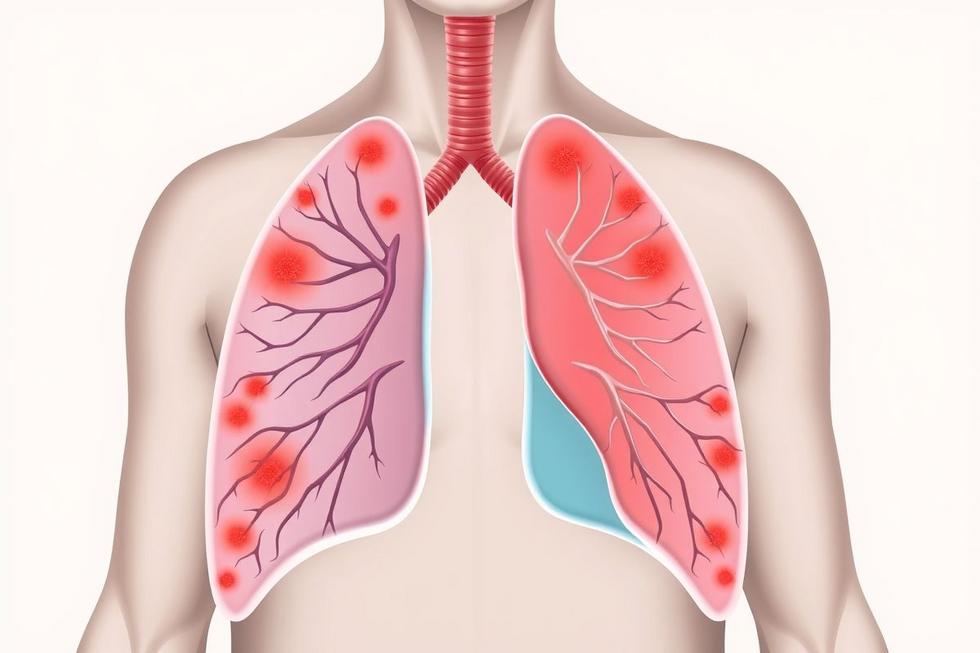

A pneumonia é uma infecção pulmonar que pode variar em gravidade e que, se não tratada adequadamente, pode levar a complicações sérias. Identificar os sintomas precocemente é essencial para garantir que os pacientes recebam o tratamento necessário o mais rápido possível. O sistema respiratório é a parte do corpo mais afetada pela pneumonia, pois a infecção provoca inflamação nos pulmões, dificultando a troca de oxigênio e causando problemas respiratórios.

Quando a pneumonia não é diagnosticada rapidamente, as consequências podem ser fatais. A infecção pode se espalhar por todo o corpo, levando a uma condição chamada sepse, que é uma resposta inflamatória grave a infeções. Por isso, saber reconhecer os sinais e sintomas da pneumonia é vital para a preservação da saúde e para evitar a evolução para quadros clinicamente mais complexos.

A pneumonia pode ser causada por diversos agentes patogênicos, incluindo bactérias, vírus e fungos. Cada tipo se comporta de maneira diferente, afetando o organismo de formas variadas. As pneumonia bacterianas são frequentemente mais graves e podem exigir tratamento com antibióticos. Entre as bactérias mais comuns estão o Streptococcus pneumoniae e o Haemophilus influenzae. Os sintomas típicos incluem febre alta, calafrios e tosse produtiva com secreção. Por outro lado, as pneumonia virais, como a que pode ser causada pelo vírus da gripe, tendem a ter um início mais gradual. A tosse pode ser seca, e a febre pode não ser tão alta quanto em infecções bacterianas.

As infecções por fungos são menos comuns, mas podem ser graves, especialmente em pessoas imunocomprometidas. Os sintomas podem se assemelhar aos de pneumonia bacteriana, mas a abordagem de tratamento geralmente é diferente, envolvendo antifúngicos. Por isso, compreender as diferenças ajuda a direcionar o tratamento correto desde o início.